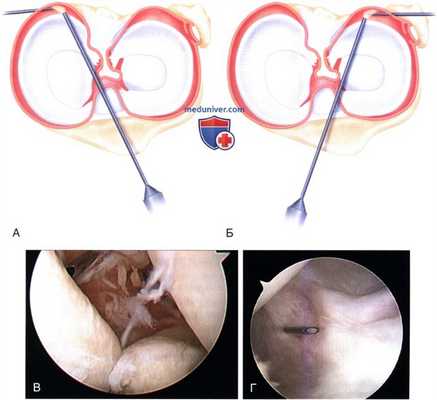

е) Через порт вводится шейвер и выполняется резекция синовиальной оболочки заднемедиального отдела коленного сустава. На рис. 8 представлена артроскопическая картина заднемедиального отдела коленного сустава (70° артроскоп находится под ЗКС и обращен в заднемедиальный отдел, определение положения заднемедиального рабочего порта с помощью спинальной иглы)

РИСУНОК 8. Локализация заднемедиального (А) и заднелатерального (Б) портов с помощью спинальной иглы и соответствующая артроскопическая картина заднемедиального отдела коленного сустава при синовиальном хондроматозе с фиксированными внутрисуставными хондромными телами (В) и в норме (Г).